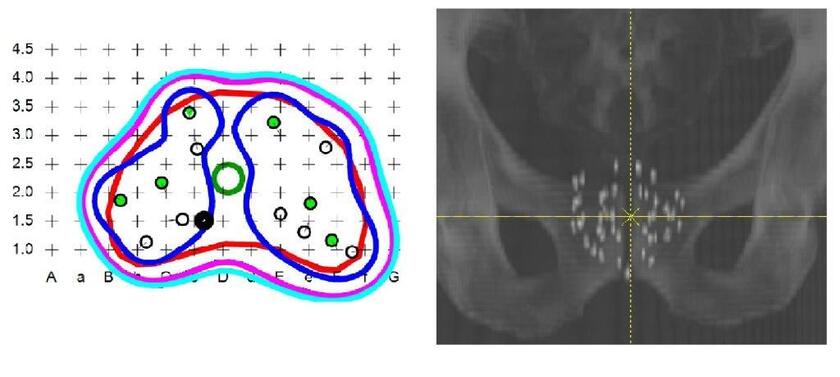

links: Bestrahlungsplan für die Seedimplantation.

rechts: Röntgenbild zur Lagekontrolle der Seeds.

Geeignete Patienten mit Prostatakrebs im frühen Stadium können hier auch eine Behandlung mit permanent eingebrachten radioaktiven Strahlern (SEED-Implantation) erhalten.